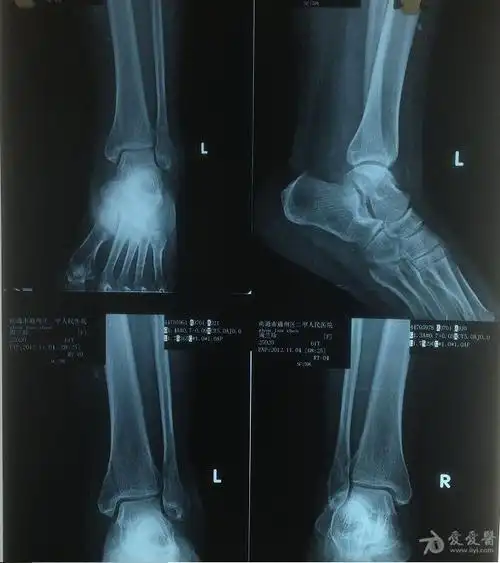

楔骨骨折

内踝骨骨折容易得创伤性关节炎吗?

内踝骨折70天是否已经康复

该内踝骨折需要手术吗

左第一锲骨骨折怎么处理